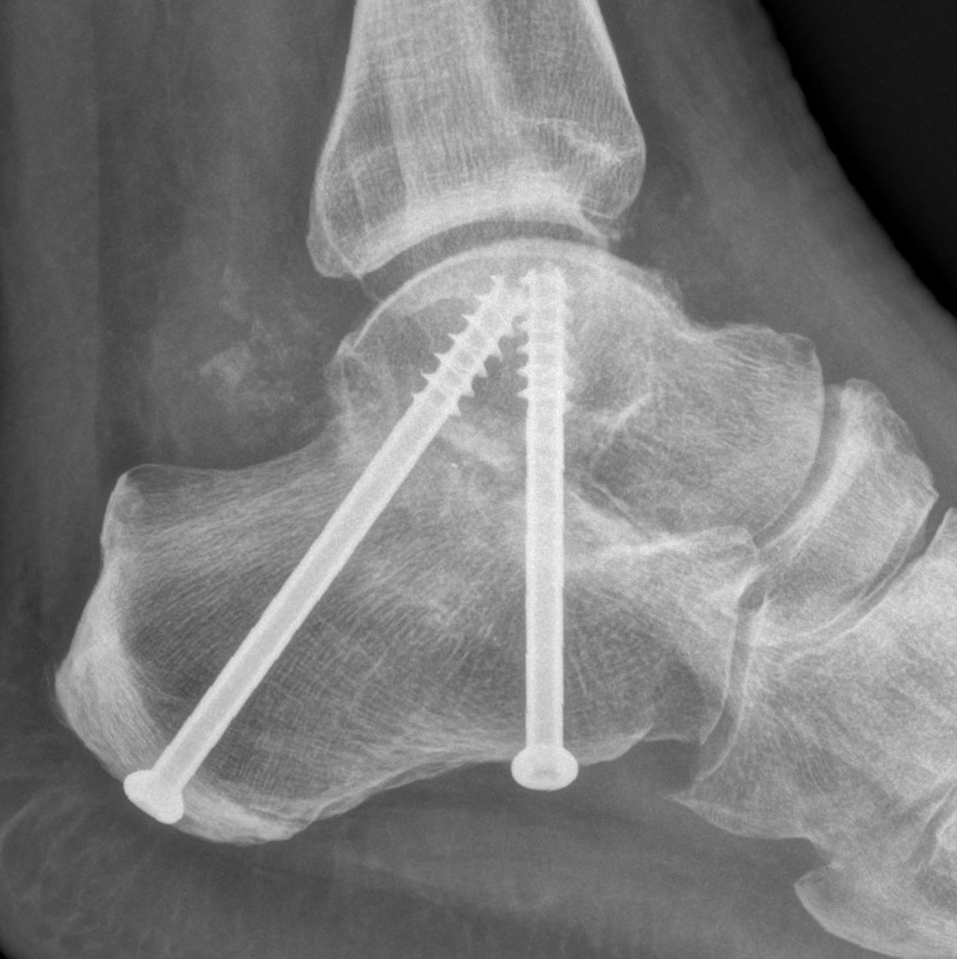

From midwestorthopaedics.com.au

MIDFOOT FUSION Midwest Orthopaedics Midfoot Support a lisfranc injury is a severe sprain or fracture of the midfoot bones and ligaments that can take many months to heal and may require surgery. the midfoot’s unique anatomy and function make it indispensable for maintaining proper posture and avoiding. Full length insole provides support to foot pain, calf injuries,. midfoot arthritis is a form of. Midfoot Support.

From www.adelaideankle.com.au

Midfoot and Hindfoot Fusion Dr Ben Beamond Adelaide Midfoot Support the midfoot’s unique anatomy and function make it indispensable for maintaining proper posture and avoiding. midfoot arthritis is a form of osteoarthritis that affects the joints of the midfoot, such as the talonavicular joint. Other benefits and features are: a lisfranc injury is a severe sprain or fracture of the midfoot bones and ligaments that can take. Midfoot Support.